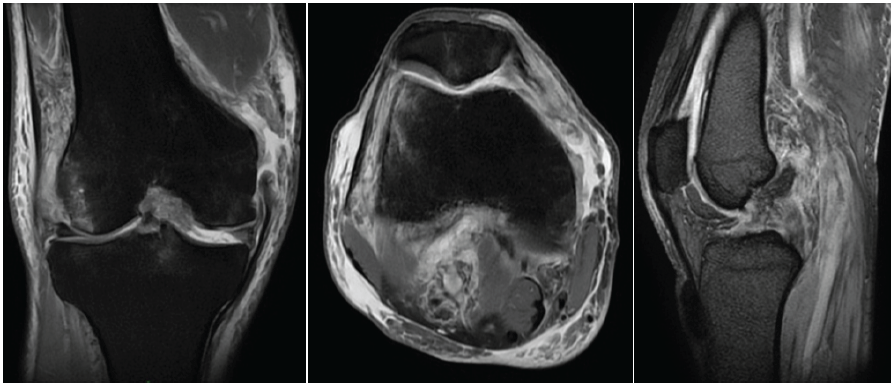

Magnetic resonance imaging (MRI) scan of the knee revealed a complete tear of the ACL, PCL, MCL, medial patellofemoral ligament (MPFL), and a grade II tear of the body of the medial and lateral meniscus.( Fig. 3)

Figure 3: Magnetic resonance imaging of the right knee showing medial collateral ligament tear at the femoral end, anterior cruciate ligament tear, posterior cruciate ligament tear, and medial patellofemoral ligament tear.